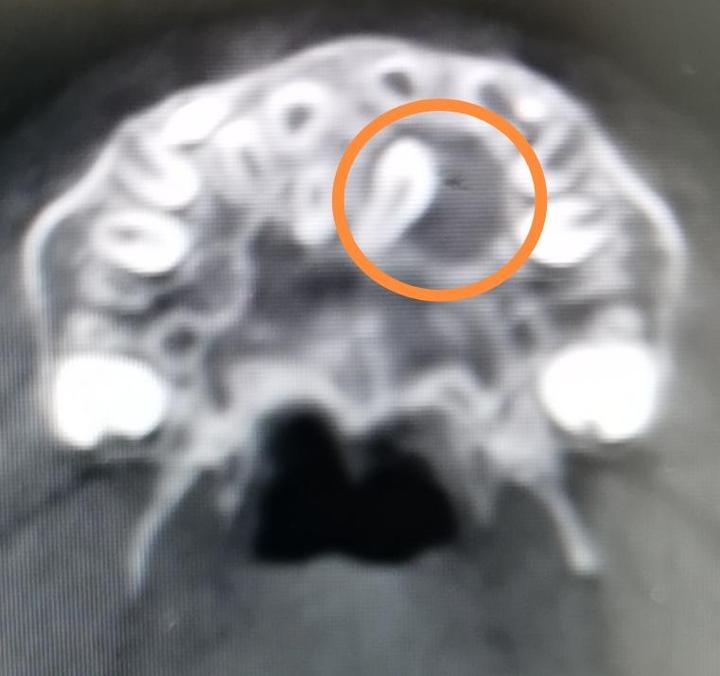

3.正常牙齿阻生